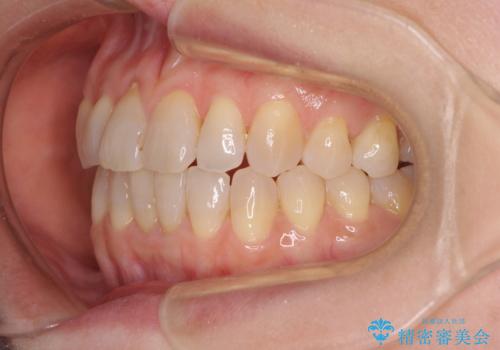

前歯の叢生と切端咬合 インビザラインによる矯正治療

- 前歯のデコボコを気にして来院された患者様です。

上下前歯の先端同士が接触する切端咬合であったため、上顎は歯列を拡大し、下顎はIPR(歯と歯の間を削る)により叢生を解消しながら歯列を小さくすることとしました。

矯正装置にはインビザラインを用いることとしました。

治療前から歯肉退縮が認められ、矯正治療により悪化する可能性が考えられたため、無理のない歯の移動と頻繁な経過観察を行いました。

切端咬合はスムーズに解消され、前歯の負担を軽減させることができました。